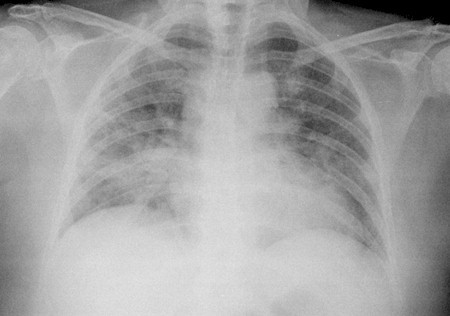

- Radiografía de tórax: Los datos de las radiografías de tórax en casos son inespecíficos e incluso sin anomalías discernibles. En casos de neumonitis por hipersensibilidad aguda y subaguda, los signos pueden ser transitorios e incluir:

- opacidades micronodulares imprecisas.

- opacidades alveolares en “vidrio esmerilado”.